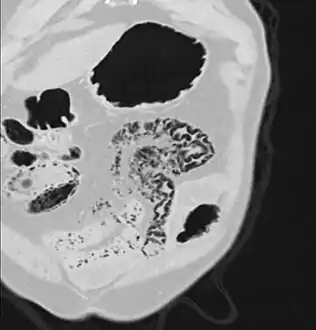

Close-up of intestine of infant showing necrosis and pneumatosis intestinalis (autopsy)

Pneumatosis intestinalis (also called intestinal pneumatosis, pneumatosis cystoides intestinalis, pneumatosis coli, or intramural bowel gas) is pneumatosis of an intestine, that is, gas cysts in the bowel wall.[1][2] As a radiological sign it is highly suggestive for necrotizing enterocolitis. This is in contrast to gas in the intestinal lumen (which is relieved by flatulence). In newborns, pneumatosis intestinalis is considered diagnostic for necrotizing enterocolitis, and the gas is produced by bacteria in the bowel wall.[3] The pathogenesis of pneumatosis intestinalis is poorly understood and is likely multifactorial. PI itself is not a disease, but rather a clinical sign. In some cases, PI is an incidental finding, whereas in others, it portends a life-threatening intra-abdominal condition.